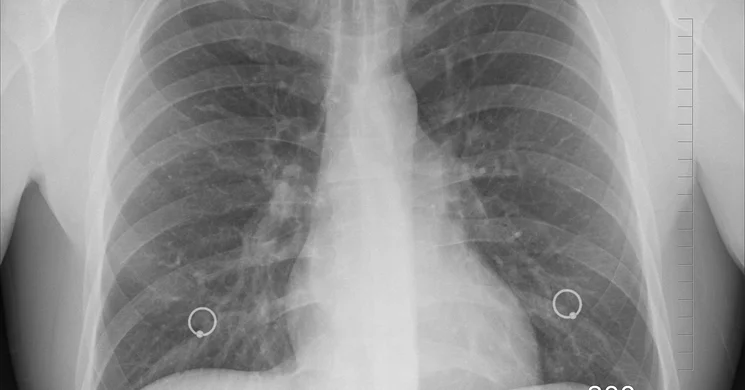

Kép forrása: Pixabay.com